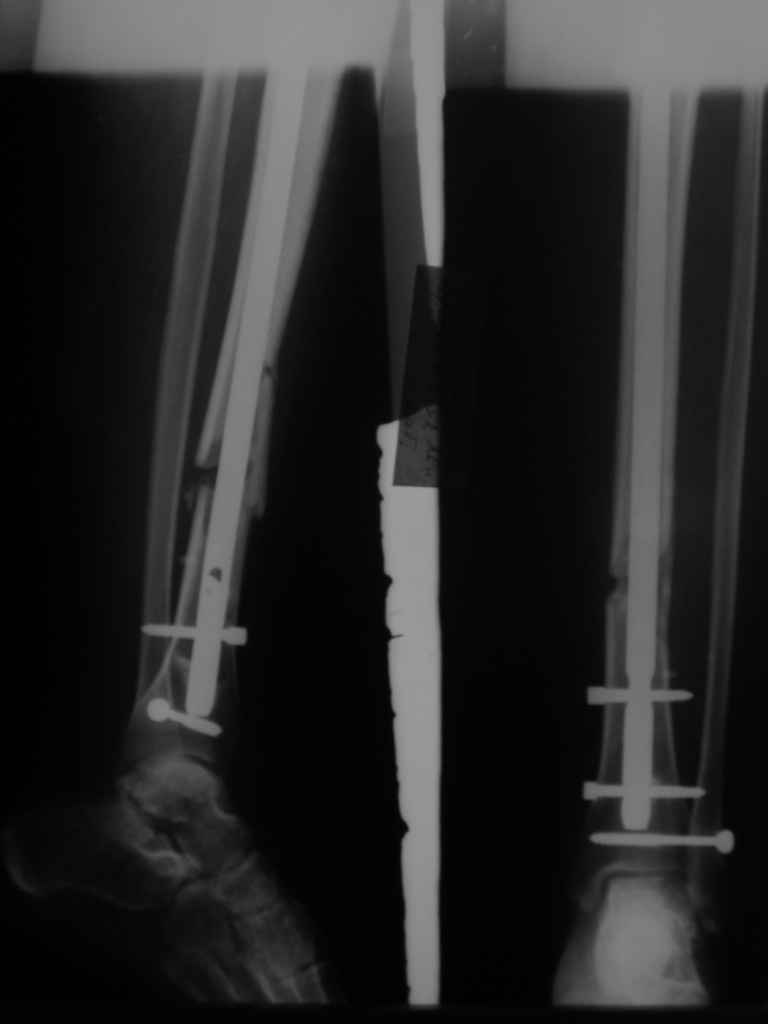

В приложении картинка пациента со сломанным внизу гвоздем. Начал лечение в другом учреждении. Еще и адвокат к тому же.

Динамизировали через 8 недель, а оно поползло больше, чем хотелось бы.